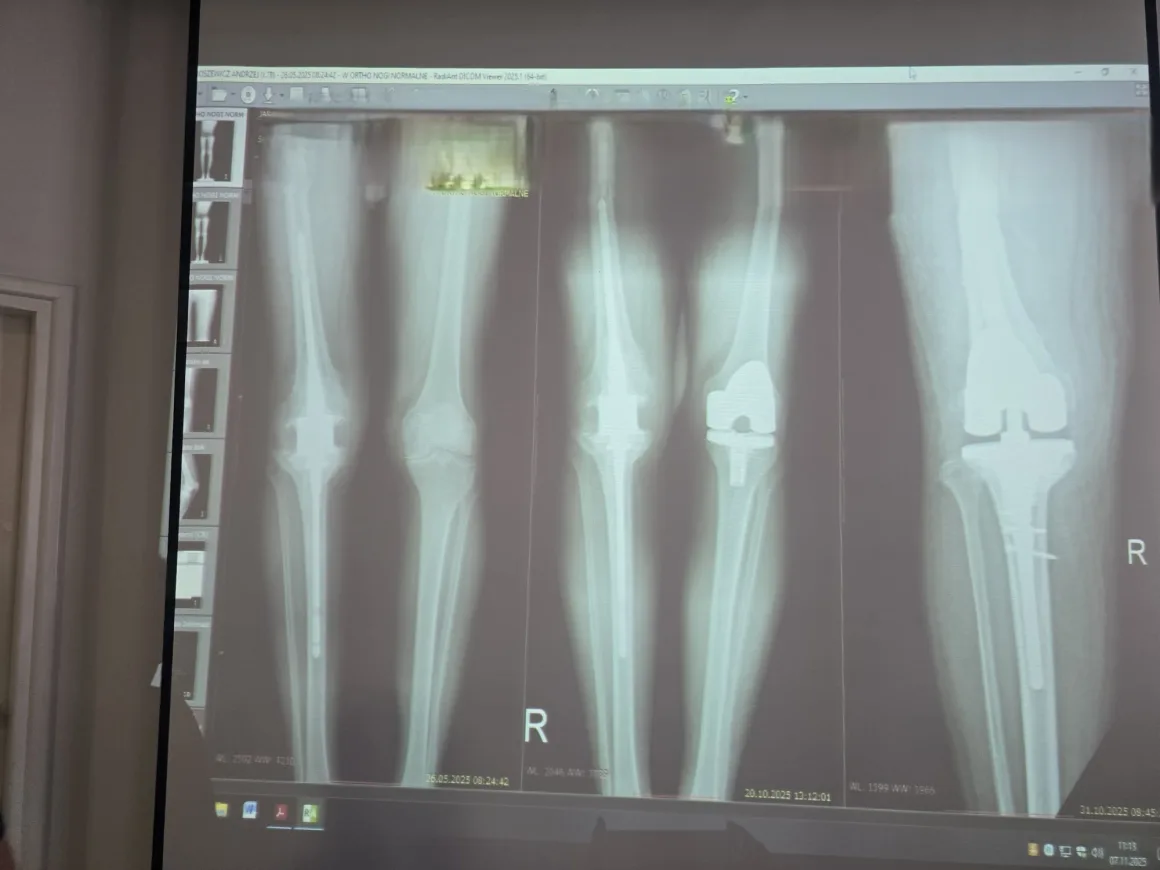

Lekarze podczas 4 godzinnej operacji usunęli gwóźdź, usunęli tkankę bliznowatą i założyli specjalną, odpowiednią dla tego chorego protezę.

– Największą trudnością w tym zabiegu było usunięcie tego gwoździa – dodaje dr Thomas Wenta, który asystował dr Kirylukowi. – Kiedy wykonaliśmy osteotomie guzowatości piszczeli, było już łatwo zgiąć nogę. Kiedy jednak guzowatość przyszyliśmy do kości, zaczął się problem, by zgiąć kolano. Wszystkie ścięgna i więzadła były mocno napięte, były zrosty. Teraz potrzebna jest rehabilitacja, bo kolano jest sztywne, ale nie z powodu metalu, ale przez naciągnięte tkanki.

Po operacji kolano się zgina w prawie 90 stopniach. Pacjent chodzi. Badanie biomechaniki chodu wykazało, że operacja się powiodła.

Dr Kiryluk przyznaje, że takich operacji wykonuje się niewiele w Polsce. W Białymstoku była to pierwsza tego typu operacja. – Uruchomienie sztywnego kolana po trzech latach – to duże wyzwanie, gdyż po takim czasie zanikają mięśnie. Takie operacje są obarczone bardzo dużym ryzykiem. Musieliśmy usunąć gwóźdź, wyciąć chore tkanki, ściąć brzeżne wyrośla kostne, żeby zyskać odpowiedni zakres ruchomości. Usunięcie gwoździa i jednoczesna protezoplastyka jest zabiegiem trudnym i ryzykownym, ale jak się udaje to jest spektakularny sukces. Co ważne wstawiliśmy protezę pierwotną (czyli taką jaką wstawią się za pierwszym razem), a nie rewizyjną (którą wstawia się przy kolejnej operacji). A to też jest trudne. Zawsze takie zabiegi mogą się skończyć infekcja i koniecznością amputacji kończyny i pacjent o tym widział.